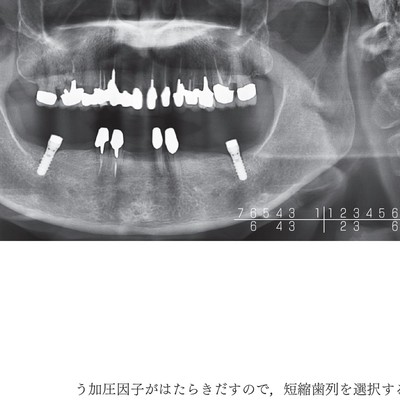

「見る目が変わる!「欠損歯列」の読み方,「欠損補綴」の設計」本多 正明 / 宮地 建夫 / 伊藤 雄策ISBN978-4-7812-0296-9定価: ¥ 16000+税#本多正明 #本多_正明 #宮地建夫 #宮地_建夫 #伊藤雄策 #伊藤_雄策 #本 #自然/医療・薬学・健康ほぼ未使用ですので、本文は汚れや汚れ千疋などもなく綺麗な状態です。写真ではわかりにくいのですがカバーに擦れや小傷があります。確認しておりますが、見落としがありましたらお許し下さいませ。喫煙者ペットおりません。ご覧いただきありがとうございます。